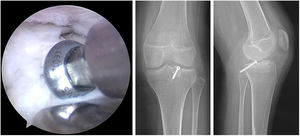

TécnicaBajo anestesia general y uso de torniquete, se realiza abordajes artroscópicos antero lateral y antero medial, se localiza abordaje postero-lateral, tomando como referencia anatómica intraarticular, el tendón poplíteo, y abordaje anterior externo longitudinal de 3cm aproximadamente a nivel de meseta tibial externa, realizando canal óseo de forma trapezoidal, donde se coloca el aloinjerto cadavérico con bloque óseo previamente preparado para encaje a presión y se fija con tornillo canulado de 4.0mm desde superior a inferior en ángulo oblicuo sin afectar a la fisis, corroborando con equipo de fluoroscopía, finalmente se sujeta el menisco mediante fijación periférica hacia la cápsula (figs. 2-6).

Finalmente, al año posoperatorio la paciente se encuentra asintomática, desarrollando sus actividades cotidianas con normalidad, con un IKDC de 70/87=80.5% y EVA 0/10, además en la radiografía anteroposterior y lateral de rodilla se evidencia consolidación de bloque óseo en la tibia y tornillo localizado de manera adecuada, por lo que se decide dar el alta médica. Paciente al año posquirúrgico refiere alivio total de síntomas en actividades cotidianas y ligera dificultad en flexión profunda (cunclillas) con resultado satisfactorio para la paciente.